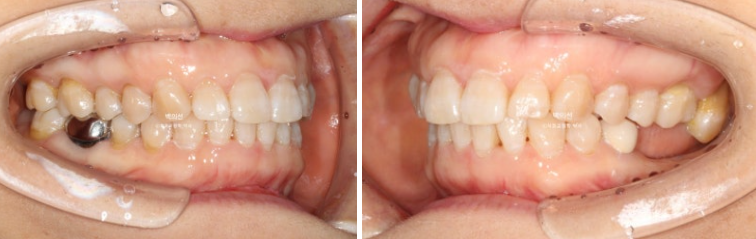

작년 9월, 앞니 돌출과 삐뚠치아 배열을 위해 오신 환자분입니다.

정면에서는 아래 앞니 일부가 윗니에 가려져 안 보일정도의 심한 과개교합을 보입니다.

좌측 아래는 어금니가 빠진 지 오래된 상태입니다.

앞니 두 개가 튀어나와 돌출이며

아래 앞니는 치아가 많이 겹쳐져 있습니다.

특히 가운데 앞니와 옆 앞니는 50% 정도가 겹쳐진 상태